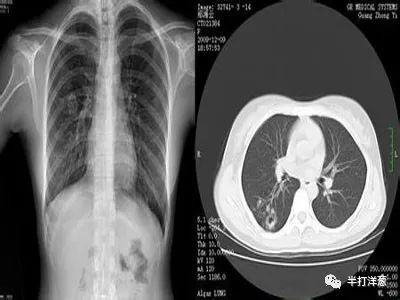

胸片没事,CT却查出肺癌,胸部体检应该怎么选?